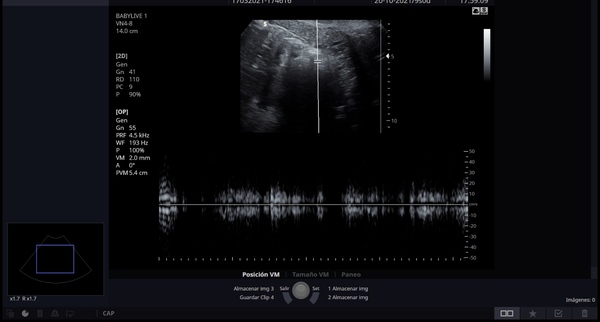

Fast forward to 17.03.2021(Around 6/7 weeks) I went for an early scan at a scan centre, not hospital, to see if could listen to heartbeat. They could only do an abdominal scan, the sonographer had trouble finding the baby and then was pretty certain could see it and picked up a "heatbeat". It sounded like a heartbeat but the scan defo didnt really look like much (Pic attached). As she was not able to get a clear view, she rebooked me for 29th.